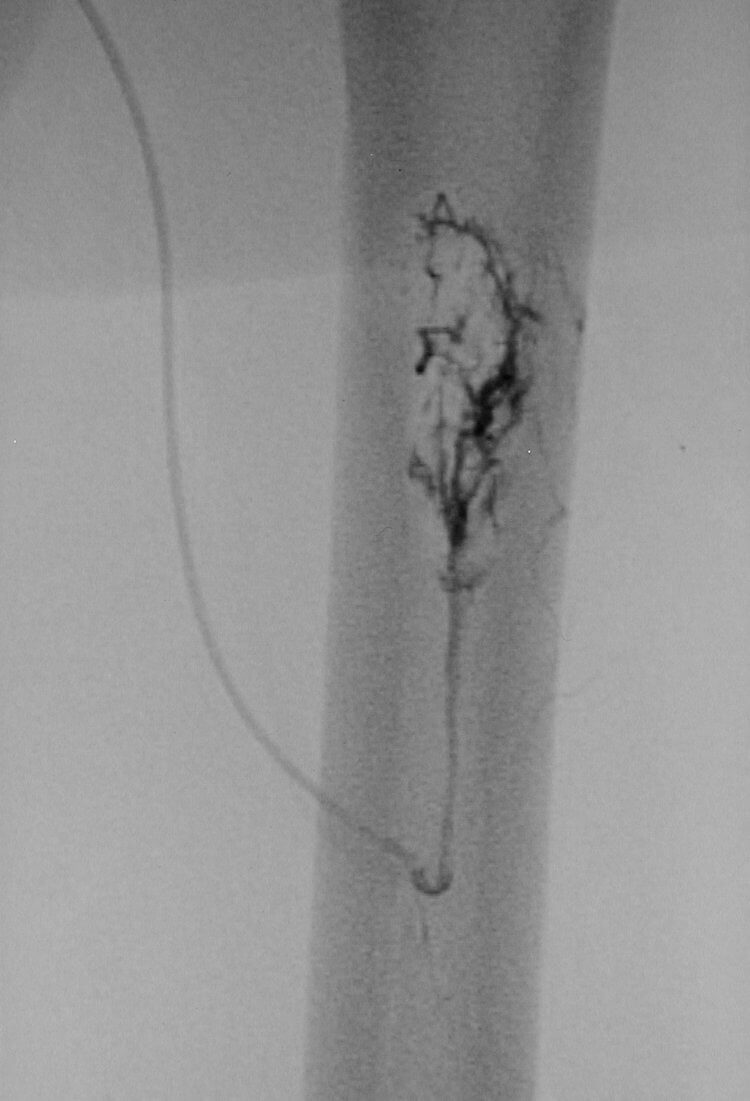

67 year old female patient with renal cell carcinoma who presents with a metastasis to the left femur for preoperative embolization.

67 year old female patient with renal cell carcinoma who presents with a metastasis to the left femur for preoperative embolization.